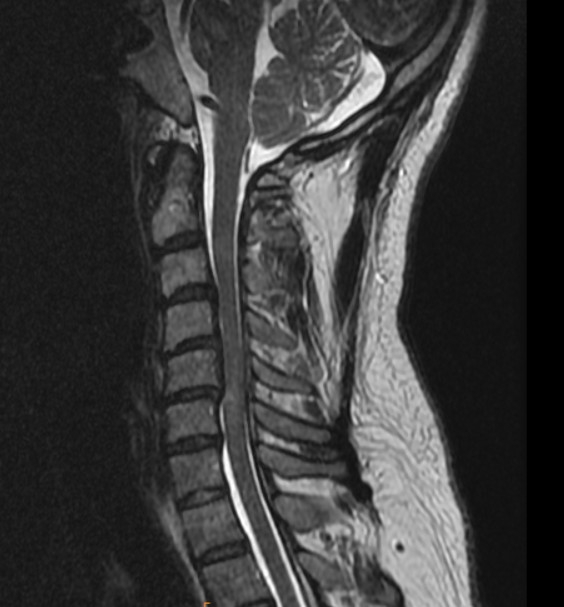

再次到大醫院檢查,照了X光、CT、MRI似乎追到問題了